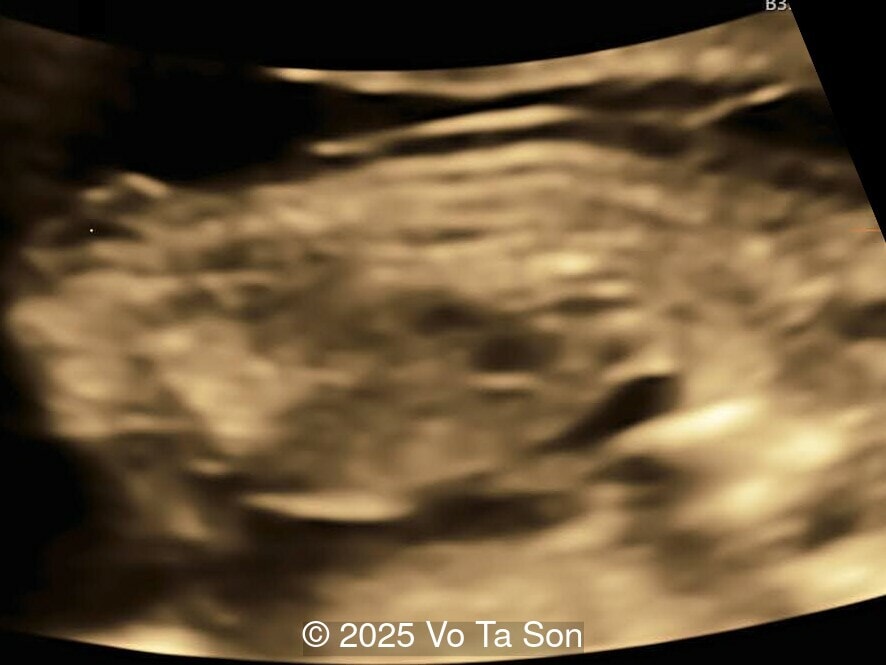

• Cystic-appearing placenta, suggestive of partial molar changes

Given the discordance between the low-risk NIPT result and the concerning ultrasound findings, chorionic villus sampling was performed. Karyotype results revealed triploidy with a 69,XXY chromosomal complement, consistent with diandric triploidy (paternal origin). This finding correlated well with the ultrasound abnormalities, particularly the cystic placenta and multiple fetal structural defects.